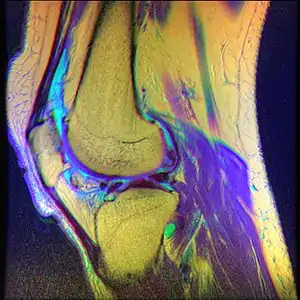

Chondromalacia patellae (also known as CMP) is an inflammation of the underside of the patella and softening of the cartilage.

Diagnostic methodMRI

Pain at the front or inner side of the knee is common in adults of all ages especially when engaging in soccer, gymnastics, cycling, rowing, tennis, ballet, basketball, horseback riding, volleyball, running, combat sports, figure skating, snowboarding, skateboarding and even swimming. The pain is typically felt after prolonged sitting.[12] Skateboarders most commonly experience this injury in their non-dominant foot due to the constant kicking and twisting required of it. Swimmers acquire it doing the breaststroke, which demands an unusual motion of the knee. People who are involved in an active lifestyle with high impact on the knees are at greatest risk. Proper management of physical activity may help prevent worsening of the condition. Athletes are advised to talk to a physician for further medical diagnosis, as symptoms may be similar to more serious problems within the knee. Tests are not necessarily needed for diagnosis, but in some situations they may confirm diagnosis or rule out other causes for pain. Commonly used tests are blood tests, MRI scans, and arthroscopy.[13]

While the term chondromalacia sometimes refers to abnormal-appearing cartilage anywhere in the body,[14] it most commonly denotes irritation of the underside of the kneecap (or "patella"). The patella's posterior surface is covered with a layer of smooth cartilage, which the base of the femur normally glides smoothly against when the knee is bent. However, in some individuals the kneecap tends to rub against one side of the knee joint, irritating the cartilage and causing knee pain.[15]

• Magnetic Resonance Imaging (MRI) – to observe cartilage deterioration.